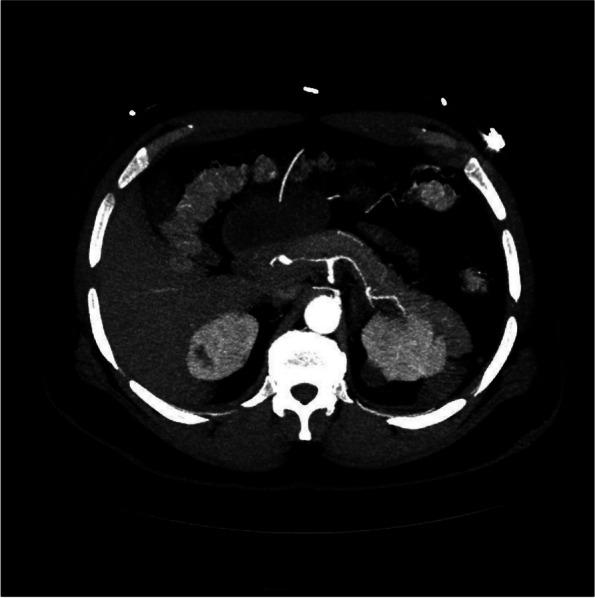

结节性多动脉炎(PAN)是一种系统性血管炎(SV),历史上被认为不会累及冠状动脉。冠状动脉造影和现代影像学显示冠状动脉狭窄和扩张,这与显著的发病率和死亡率相关。PAN 中的冠状动脉受到全身炎症引起的加速动脉粥样硬化的影响,这增加了固有动脉炎过程的风险。传统的动脉粥样硬化危险因素无法准确估计风险。很少有报道描述冠状动脉的病理变化,最佳治疗方法也受到限制。

冠状动脉受累的严重程度难以通过实验室监测来评估,但冠状动脉疾病与几种临床症状相关。弗雷明汉危险因素不能充分估计疾病负担。要将动脉粥样硬化与动脉炎分开,需要先进的血管造影方法。治疗包括抗凝、免疫抑制和血运重建。经皮冠状动脉介入治疗(PCI)一直是主要的治疗方法,尽管支架置入后由于管腔直径的不规则变化和新生内膜形成的报告,支架的应用受到限制。

当移植物选择避开 SV 的血管区域时,冠状动脉旁路移植术(CABG)提供了明确的治疗方法。除了回顾、更新和讨论文献外,我们还报告了一种新型的 CABG 构型。越来越多的证据表明,特定的临床症状提示存在冠状动脉受累。